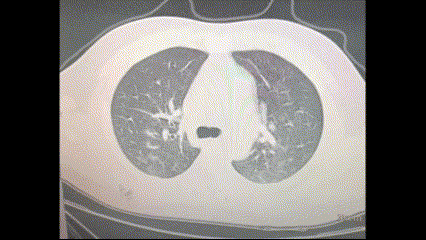

Tomodensitométrie des poumons dans un cas confirmé de Covid-19.

Les amas blancs apparaissant sur les tomographies et les radiographies sont des indices d’inflammation et de pneumonie, deux signes inquiétants souvent observés dans les cas de Covid‑19 modérés à sévères.

Tomodensitométrie des poumons fournie par un patient chinois ayant développé des symptômes de type grippe à la mi-décembre 2022. (Epoch Times)